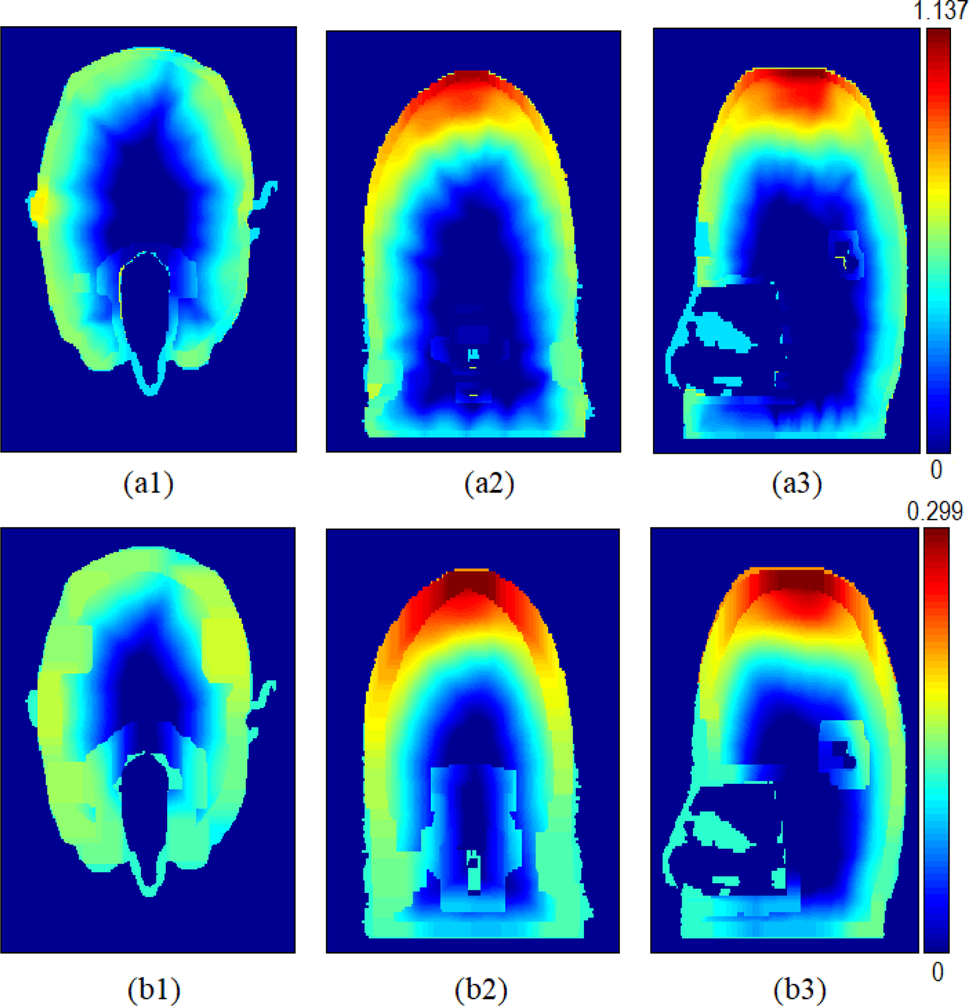

The SAR1g and SAR10g distributions in the x–y, x–z, and y–z cross sections of the human head model are shown for 2.4 and 5.8 GHz in Figs 7 and 8, respectively. The maximum values of SAR1g and SAR10g at resonance frequencies are tabulated in Table 4. The SAR1g and SAR10g values reported in Table 4, except the value at 2.4 GHz, are less than 1.6 W/kg [Reference Ulcek and Cleveland11] for 1-g of tissues and 2 W/kg [12] for 10-g of tissue, respectively. At 2.4 GHz, the maximum SAR1g value just above 1.6 W/kg is within an acceptable range according to the studies in the literature. It can be seen from Figs 7 and 8 that the maximum SAR values occur on the top of the human head due to the wearable antenna on the flat top textile beret. It is also realized from these figures the SAR1g and SAR10g distributions appear in a good correlation. It can be realized that the resonance frequencies affect the maximum SAR1g and SAR10g values and SAR distributions.

Fig. 7. (a1), (a2), (a3) SAR1g and (b1), (b2), (b3) SAR10g (W/kg) distributions on the x–y, x–z, and y–z cross sections of the human-head model for 2.4 GHz.

Fig. 8. (a1), (a2), (a3) SAR1g and (b1), (b2), (b3) SAR10g (W/kg) distributions on the x–y, x–z, and y–z cross sections of the human-head model for 5.8 GHz.